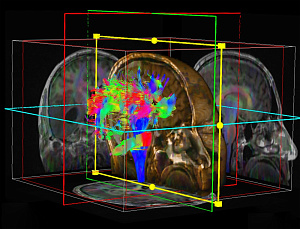

Диабетическая полинейропатия

Диабетическая полинейропатия (ДПН) – патогенетически связанное с сахарным диабетом сочетание синдромов поражения нервной системы. Частота среди лиц с СД 2 типа достигает 70-90%.

ДПН классифицируется в зависимости от преимущественного вовлечения в процесс спинномозговых нервов (периферическая нейропатия) и/или вегетативной нервной системы (автономная нейропатия).

Диабетическая дистальная симметричная сенсорно-моторная полинейропатия — самый частый вариант периферической диабетической нейропатии. Типичными симптомами являются ощущение жжения, «бегания мурашек», боли в голенях и стопах, ночные судороги мышц. При неврологическом обследовании выявляются ослабление ахилловых рефлексов, нарушение чувствительности по типу «носков» и «перчаток», снижение проприоцептивной чувствительности. Важно, что при поздней диагностики патологии развиваются такие осложнения язвы стоп, которые могут приводить к гангрене (диабетическая стопа) и часто к ампутациям. В лечении эффективны трициклические антидепрессанты (амитриптилин) в качестве обезболивающих препаратов, альфа-липоевая кислота и витамины группы В на фоне активного контроля уровня гликемии.

Автономная нейропатия приводит к дисрегуляции витальных функций и поддержания гомеостаза, что определяет течение и структуру смертности при СД 2 типа.

К основным клиническим проявлениям кардиоваскулярной автономной нейропатии относятся тахикардия покоя («фиксированный» пульс, часто ранний признак развивающейся ДПН), аритмии (нейропатическое удлинение интервала Q–T и др.), ортостатическая гипотензия, безболевая ишемия миокарда (БИМ), артериальная гипретензия (повышение активности симпатического отдела нервной системы, вызванное парасимпатической дисфункцией; отсутствие снижения АД в ночное время).

Наиболее тяжелым осложнением кардиоваскулярной автономной нейропатии является внезапная смерть.

Методы диагностики кардиоваскулярной автономной нейропатии включают: исследование кардиоваскулярных рефлексов (тест Вальсальвы, тест Шелонга и др.), суточное мониторирование АД, холтеровское мониторирование ЭКГ, измерение корригированного интервала QT и дисперсии интервала Q.